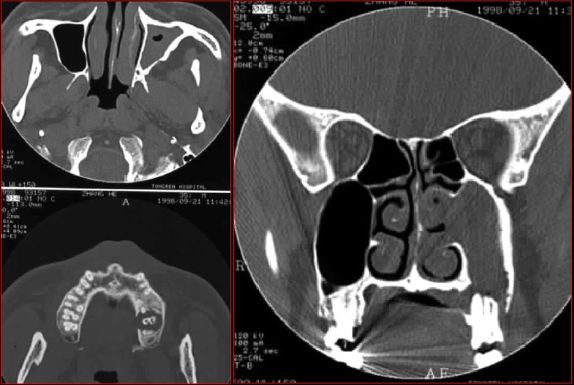

急性鼻窦炎

筛窦异物伴急性感染